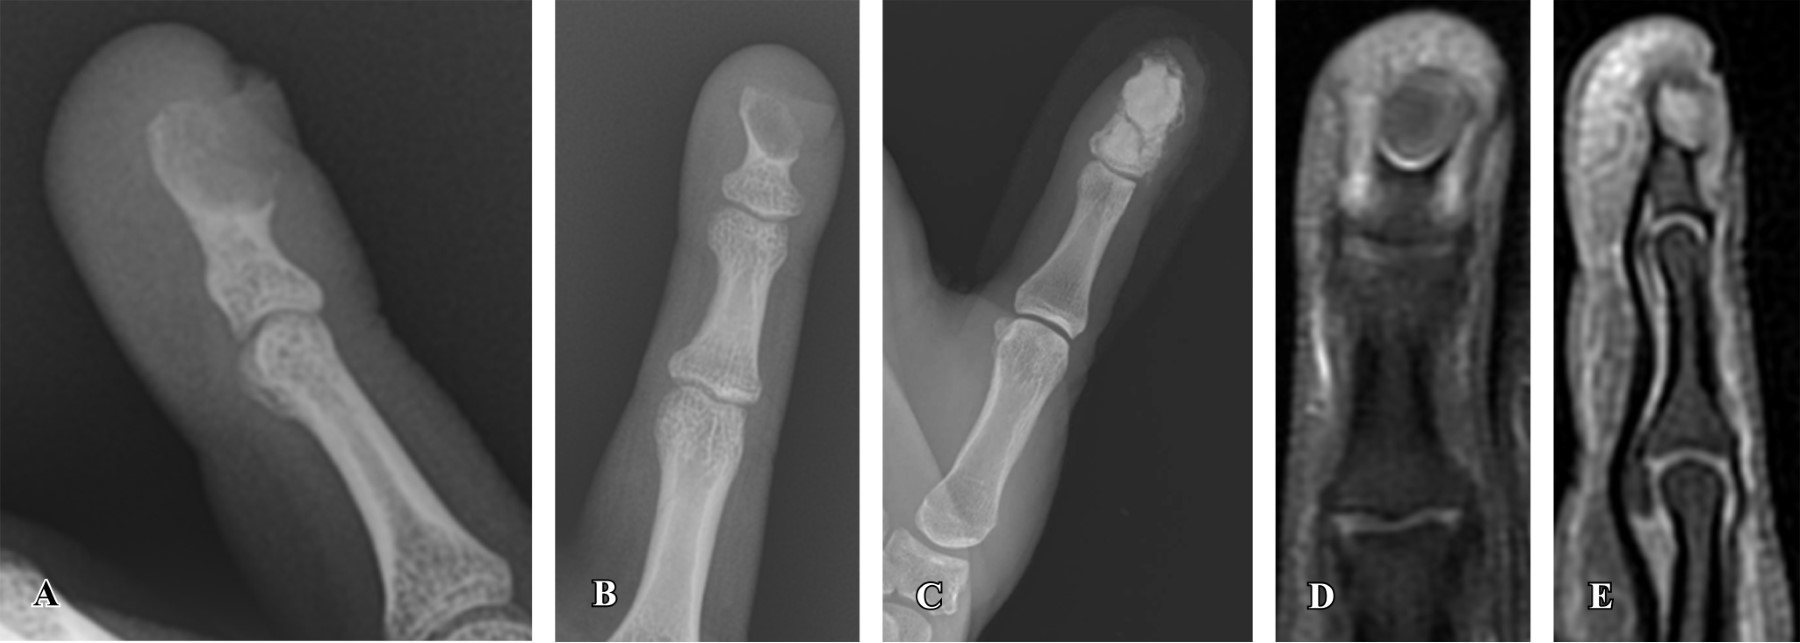

La evolución postoperatoria fue buena tanto clínica como analíticamente. Los cultivos fueron negativos. Fue la anatomía patológica la que sugirió la presencia de un quiste epidermoide sobreinfectado (Figura 2). Actualmente la paciente lleva seis meses de evolución, con correcto estado local y remodelación ósea (Figura 3).

Un diagnóstico certero se obtiene mediante el estudio anatomopatológico, debido a la baja especificidad tanto de la clínica como de las pruebas de imagen. Es característica, a nivel histológico, la presencia de una capa externa de epitelio escamoso estratificado que recubre una estructura quística central que contiene células epiteliales queratinizadas.14 Esta anatomía patológica tan característica permite diferenciar al quiste epidermoide del resto de entidades que conforman el diagnóstico diferencial, entre las que destacan: tumores de células gigantes, quistes óseos aneurismáticos, encondromas, metástasis y osteomielitis.15

Figura 2